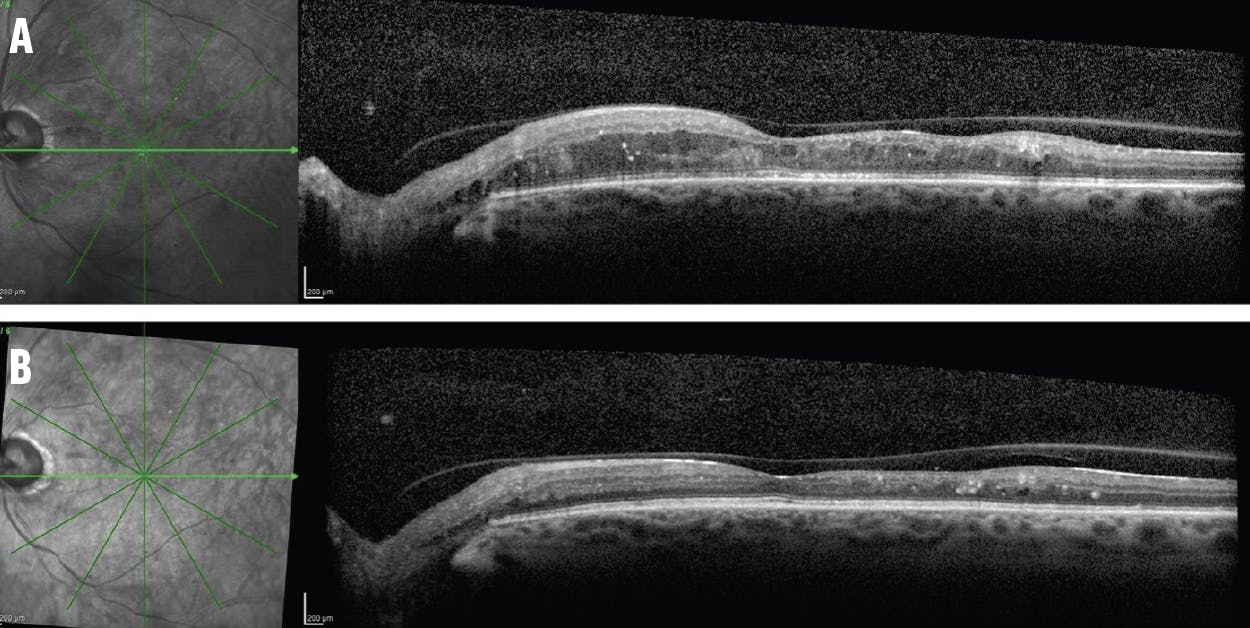

One month later, there was no progression of the subretinal fluid in the right eye, and I continued to observe the patient. Eight months after PRP, I noted regression of the TRD in the right eye and a VA of 20/20 (Figure 5). The left eye underwent oil removal 5 months after the initial repair; 3 months after the oil removal, the retina was attached, and VA improved to 20/70 OS.

<p>Figure 5. The initial OCT scan of the right eye of the patient in Figure 4 (A) showed minimal subretinal fluid that slightly progressed 1 month after PRP (B), but regressed over time. The subretinal fluid was out of the macula and the patient was stable 8 months after presentation (C). The OCT scan of the left eye at presentation (D) and 8 months later after surgical repair (E). VA in that eye improved from hand motion to 20/70 at the last visit.</p>

Figure 5. The initial OCT scan of the right eye of the patient in Figure 4 (A) showed minimal subretinal fluid that slightly progressed 1 month after PRP (B), but regressed over time. The subretinal fluid was out of the macula and the patient was stable 8 months after presentation (C). The OCT scan of the left eye at presentation (D) and 8 months later after surgical repair (E). VA in that eye improved from hand motion to 20/70 at the last visit.